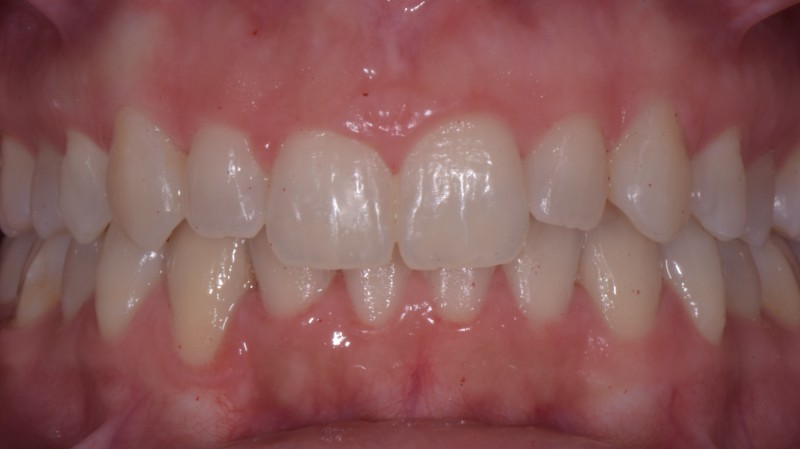

Prima e dopo il trattamento

Trascina il cursore per confrontare il risultato ottenuto.

Dopo il trattamento Prima del trattamento

Ortodonzia con mascherine trasparenti

Ortodonzia invisibile

Paziente: Donna, 17 anni